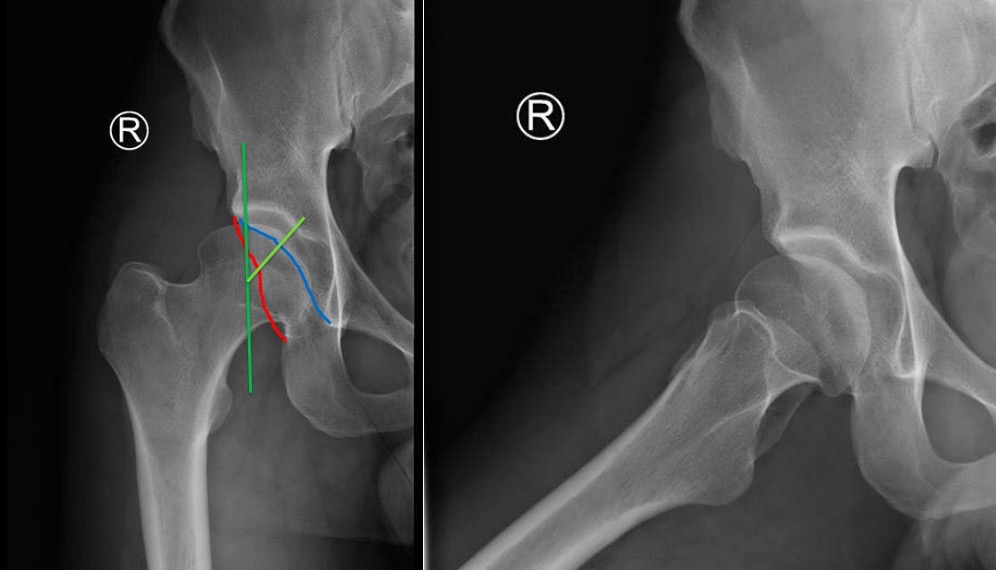

На представленном снимке (frog lateral) хорошо можно увидеть шейку и головку, но для данной патологии требуется false profile view! Для удобства приложил некоторые укладки: false profile и снимок с нормальными параметрами сустава (синими указаны центр край угол). Здесь имеется измененная и деформированная диспластическая форма головки, где огромный размер, выходя за пределы вертлужной впадины, создает иллюзию подвывиха. Очень узкая нагрузочная площадь и почти негативный (center-edge angle of Wiberg), потому что вертикаль (зеленая) от центра головки проходит с латеральной стороны. Контур передней стенки (синий) показывает что покрывает головку мало, а задняя стенка (красная) больших размеров доказывает что сустав развернут кпереди. Возможно за счет укладки, на рентгене слева шейка вроде короткая.

Для определения диагноза, кроме рентген снимков, необходим клинический осмотр. При таком суставе внутренняя ротация конечности увеличивается, а наружная ротация лимитирована. Чрезмерная флексия и ротация покажет симптомы повреждения лабрального хряща.